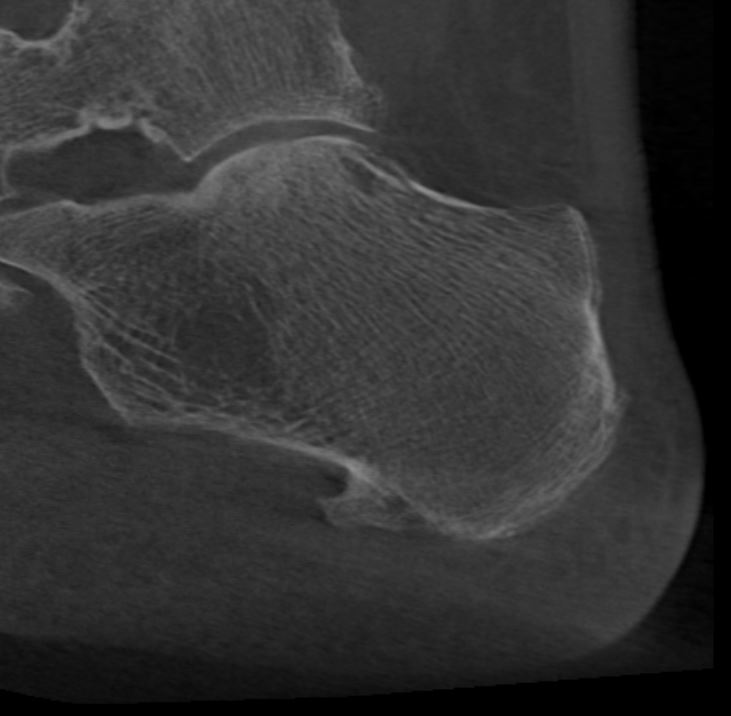

Home Schwerpunkte Krankheitsbilder Plantarfasziitis und Fersensporn – Schmerzen unter der Ferse loswerden! Digitale Volumentomografie Plantarfasziitis großer Fersensporn sagital

Digitale Volumentomografie Plantarfasziitis großer Fersensporn sagital